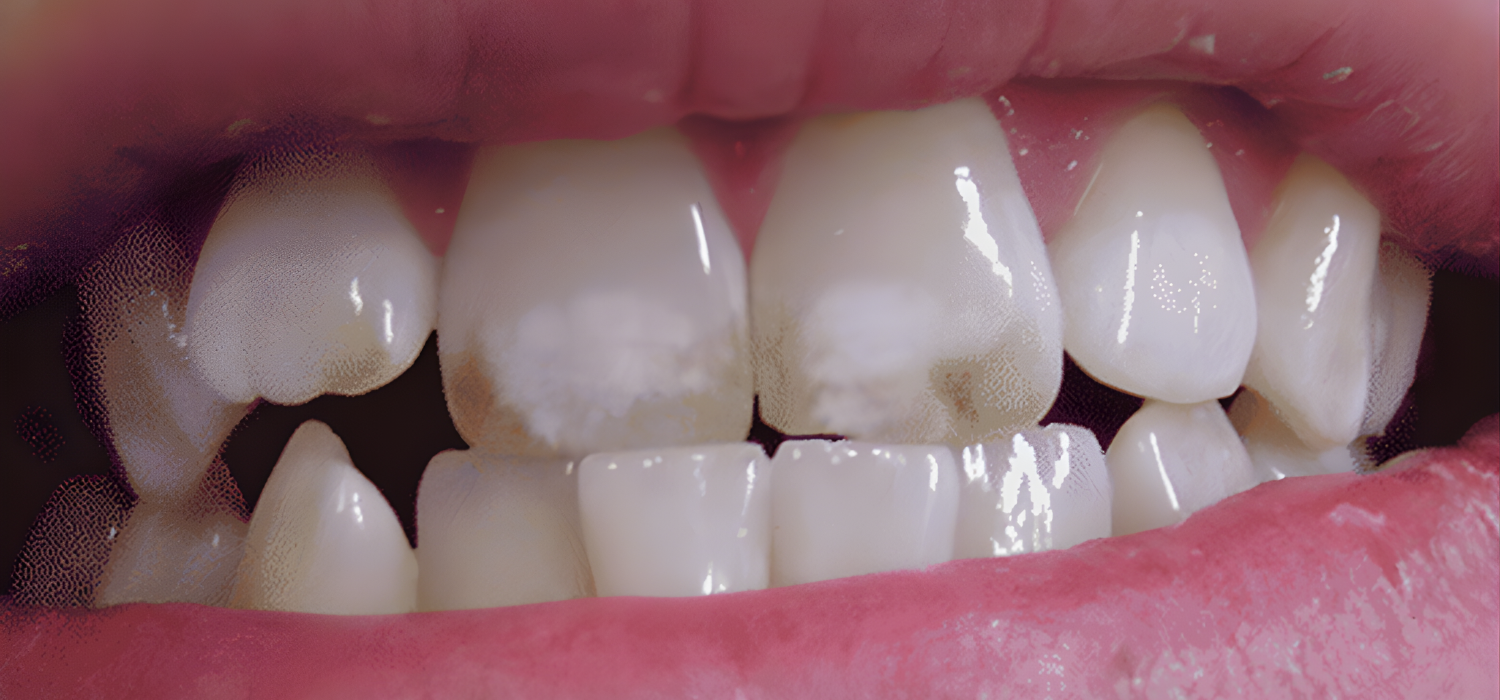

- Eruptive stage – Teeth emerge with a chalky, opaque appearance.

- Questionable – Slight, often unnoticed white spots.

- Very Mild – Small, scattered opaque areas; usually only cosmetic concern.

- Mild – More extensive white opacity covering < 50 % of the surface.

- Moderate – Opaque areas > 50 % with occasional brown staining.